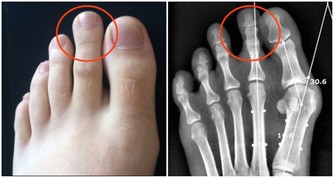

小貼士:痛風怎麼吃?

高嘌呤食物,高尿酸和痛風的人應該完全避免;

嘌呤食物,應該嚴格限量,在急性發作期不能食用;低嘌呤食物,可以放心食用。